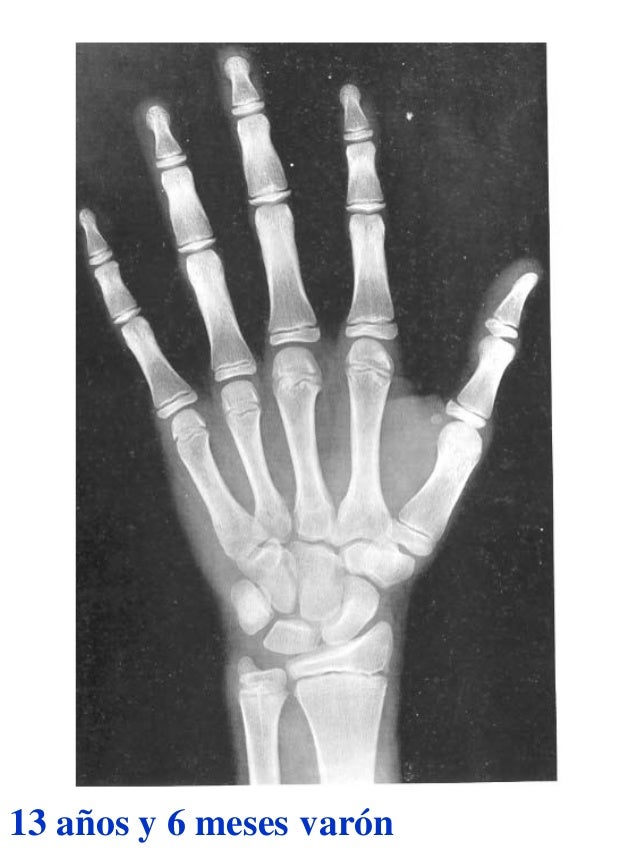

PLoS ONE 14(9):Įditor: Stephen Raverty, Animal Health Centre, CANADA In conclusion, knowledge of the lifespan and the onset of sexual maturity for each species will allow this model to be applied to other cetaceans, facilitating age estimation via pectoral radiography in future research.Ĭitation: Barratclough A, Sanz-Requena R, Marti-Bonmati L, Schmitt TL, Jensen E, García-Párraga D (2019) Radiographic assessment of pectoral flipper bone maturation in bottlenose dolphins ( Tursiops truncatus), as a novel technique to accurately estimate chronological age. This diagnostic tool could also be applied to diagnose atypical ossification patterns consistent with nutritional, developmental or growth abnormalities, and identifying subclinical health issues. Managed care dolphin ages could be properly estimated with decreasing precision from within 3 months in animals 30 years old. Completion of epiphyseal closure of the long bones correlated with average sexual maturity. Third order polynomial regression calculated separate age predictor formulas for male and female dolphins, with females reaching sexual maturity earlier than males. The most informative areas to evaluate morphologically were the metaphyseal regions of the radius and ulna, and the proximal and distal epiphysis of metacarpals II and III. A numerical score from -1 to 8 was assigned to 16 anatomic locations on the pectoral radiograph, to create a formula to estimate age. A database of 126 radiographs from 94 dolphins of known chronological age was utilized to establish the stages of skeletal ossification over time. Establishing a non-invasive method of accurately aging bottlenose dolphins across the entire age range is important to long term conservation efforts to understand health status, lifespan, reproduction and survivability. These methods are inaccurate in dolphins > 13 years old, due to overlapping of the growth layer groups in dolphins and worn teeth. The most frequently utilized methods to age bottlenose dolphins ( Tursiops truncatus) include tooth extraction counting dental growth layer groups and dental radiography. Accurate age estimation in wildlife conservation is an important diagnostic tool in the interpretation of biological data, necropsy examination, reproductive status and population demographics.